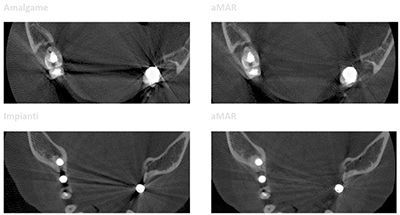

Программное обеспечение NewTom NNT предлагает все функции, необходимые для выполнения, обработки, вывода на экран и передачи 2D и 3D результатов обследования. NNT также предоставляет различные режимы и функции приложения, специально предназначенные, чтобы планировать лучшее лечение в области имплантологии, эндодонтии, пародонтологии и рентгенографии, а также в челюстно-лицевой хирургии.

GO 2D/3D имеет один собственный 16-битный датчик, который создает 2D и 3D изображения с тысячами уровней серого. Качество изображения обеспечивается передовыми алгоритмами и протоколами, а также высокотехнологичной последовательностью изображений. Высокочастотный генератор импульсного излучения регулирует экспозицию для получения наилучшего сканирования с минимальной дозой. Кроме того, система коллимации цефалометрического обследования основана на автоматическом перемещении турели, которая поворачивает и опускает датчик, создавая отверстие для рентгеновских лучей, направленных на 2D-датчик на теле радиографическом рычаге. Благодаря пяти контактным точкам поддержка головки 3D-сканирования помогает персоналу правильно и комфортно позиционировать пациента. Точки фронтального и бокового контакта могут быть отрегулированы таким образом, чтобы максимально повысить стабильность пациента во время сканирования и, следовательно, качество полученных данных. Специальный протокол позволяет проводить томографическое сканирование рентгенологических шаблонов, протезов, моделей или оттисков после их установки на специальную подставку.

GO 2D/3D имеет собственный одиночный 16-битный сенсор, который создает 2D и 3D изображения с тысячами уровней серого. Качество изображений обеспечивается продвинутыми алгоритмами и протоколами, а также высокотехнологичным секвенированием изображения. Высокочастотный генератор импульсного излучения настраивает облучение таким образом, чтобы добиться лучшего сканирования с минимальными дозами.